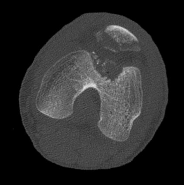

Question 10:

A 45-year-old male sustains a high-energy Schatzker IV tibial plateau fracture. Given the classic displacement pattern of this specific injury, which of the following is the most appropriate surgical approach and fixation strategy to properly neutralize the deforming forces?

Correct Answer: Posteromedial approach with a medial buttress (anti-glide) plate

Explanation:

A Schatzker IV fracture involves the medial tibial plateau and is typically the result of high-energy varus forces, often combined with an axial load. The primary deforming force drives the medial fragment into varus and posterior subluxation. The biomechanically sound treatment requires a posteromedial approach with a medial buttress (or anti-glide) plate to physically resist the varus and posterior displacement.